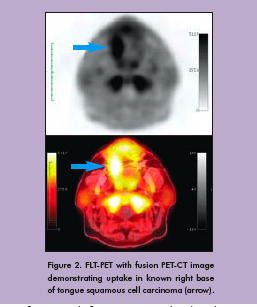

To date, our team has used FDG and FLT with PET-CT to evaluate three patients (Figure 2). All patients tolerated the protocol well. Figure 3 shows FDG and FLT PET images in one patient by both standard uptake methods and by Patlak analysis. Corresponding pathology in this patient demonstrated an increased Ki-67 index in both the primary tumor and reactive lymph nodes (Figure 4). Primary tumor, metastatic lymph nodes, and reactive lymph nodes all showed increased FDG and FLT uptake (Figure 5). Additional data are needed to determine probability and proliferation thresholds for application to radiation treatment planning. However, given the overlap in uptake values between tumor and reactive lymph nodes, this finding underscores the importance of determining thresholds based on pathologic correlation to improve the accuracy of radiation treatment planning volumes.

We prospectively enrolled patients with known head and neck cancer who are eligible for tumor and lymph node resection for sequential two-day pre-operative PET-CT imaging with 18F-fluorodeoxyglucose (FDG) and 18F-fluorothymidine (FLT). The patient’s position was repeated by the use of a thermoplastic mask with the neck supported on a Timo cushion mounted on a carbon fiber board. We acquired images in list-mode using a Siemens Biograph 16 PET-CT scanner (Siemens Medical Solutions USA, Inc., Malvern, PA) and used software provided by the vendor to reframe them as two dynamic series: 0-10 minutes post-injection over the heart and 15-60 minutes post-injection over the head and neck. A whole body PETCT scan was then performed, followed by a high-count head and neck PET-CT image. We calculated maximum standardized uptake values (SUVs) over specific regions of interest (TrueD software on a syngoMMWP system, Siemens Medical Solutions USA, Inc.). For Patlak graphical analysis, we performed all reconstructions using the same FORE+2D-OSEM algorithm provided by the scannermanufacturer with four iterations and eight subsets. We generated an arterial input function using a left-ventricular region, derived-time activity curve for 0-10 minutes post-injection and measured activity from five venous blood samples thereafter up to one hour post-injection. In the case of FLT, the FLT metabolite fraction was corrected using solid phase extraction and separation. This input function was used to perform Patlak analysis with the dynamic head and neck dataset of 15-60 minutes post-injection. Patlak Ki (slope) images were generated using OASIS, IDL-based tools developed at the National Institutes of Health, Bethesda, MD.